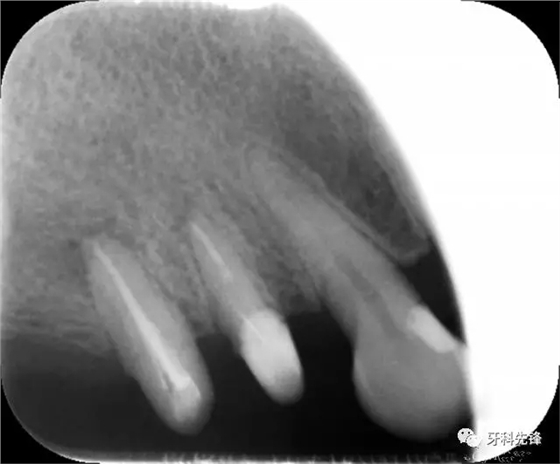

圖1術(shù)前X光片

640.webp.jpg